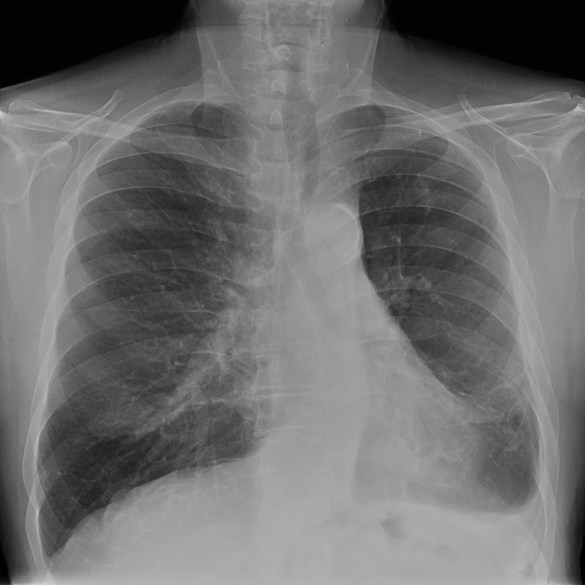

CASO: Febrícula y tos de 4 días de evolución.

Hallazgos:

- En la placa PA se observa una asimetría en los hilios pulmonares, el hilio izquierdo tiene una densidad aumentada.

- Tras examinar la placa lateral se observa un aumento de densidad en la columna que puede ser compatible con una condensación, es el signo de la desnificación vertebral.

SIGNO DE LA DENSIFICACIÓN VERTEBRAL: En la radiografía lateral normal, la densidad de la columna torácica tiende a disminuir desde la parte superior hasta el diafragma; la alteración de ese patrón por la presencia de una densidad superpuesta a la columna, indica la existencia de una consolidación pulmonar. Este signo adquiere especial valor cuando en la proyección posteroanterior la consolidación está oculta en el espacio retrocardíaco o en la base pulmonar.